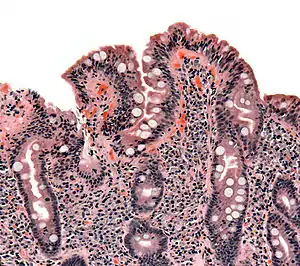

The inflammatory process, mediated by T cells, leads to disruption of the structure and function of the small bowel's mucosal lining and causes malabsorption as it impairs the body's ability to absorb nutrients, minerals, and fat-soluble vitamins A, D, E, and K from food. Lactose intolerance may be present due to the decreased bowel surface and reduced production of lactase but typically resolves once the condition is treated.

Alternative causes of this tissue damage have been proposed and involve release of interleukin 15 and activation of the innate immune system by a shorter gluten peptide (p31–43/49). This would trigger killing of enterocytes by lymphocytes in the epithelium.[28] The villous atrophy seen on biopsy may also be due to unrelated causes, such as tropical sprue, giardiasis and radiation enteritis. While positive serology and typical biopsy are highly suggestive of coeliac disease, lack of response to diet may require these alternative diagnoses to be considered.[40]

The classic pathology changes of coeliac disease in the small bowel are categorised by the "Marsh classification":[98]

- Marsh stage 0: normal mucosa

- Marsh stage 1: increased number of intra-epithelial lymphocytes (IELs), usually exceeding 20 per 100 enterocytes

- Marsh stage 2: proliferation of the crypts of Lieberkühn

- Marsh stage 3: partial or complete villous atrophy and crypt hypertrophy[99]

- Marsh stage 4: hypoplasia of the small intestine architecture

Marsh's classification, introduced in 1992, was subsequently modified in 1999 to six stages, where the previous stage 3 was split in three substages.[100] Further studies demonstrated that this system was not always reliable and that the changes observed in coeliac disease could be described in one of three stages:[18][101]

- A representing lymphocytic infiltration with normal villous appearance;

- B1 describing partial villous atrophy; and

- B2 describing complete villous atrophy.

The changes classically improve or reverse after gluten is removed from the diet. However, most guidelines do not recommend a repeat biopsy unless there is no improvement in the symptoms on diet.[40][90] In some cases, a deliberate gluten challenge, followed by biopsy, may be conducted to confirm or refute the diagnosis. A normal biopsy and normal serology after challenge indicates the diagnosis may have been incorrect.[40]

In untreated coeliac disease, villous atrophy is more common in children younger than three years, but in older children and adults, it is common to find minor intestinal lesions (duodenal lymphocytosis) with normal intestinal villi.[11][25]